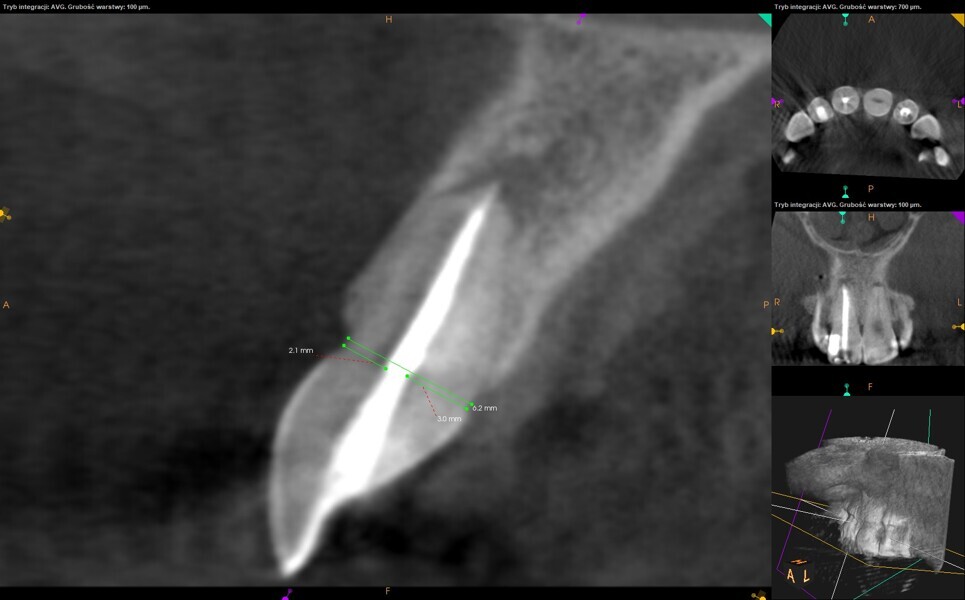

The recall appointment took place four months after treatment. Healing of the periapical tissue was observed. Despite the limitations of the CBCT imaging related to the voxel size (0.1 mm), the size of the access cavity was found to be 1.1 mm ± 0.2 mm, confirming the measurement performed during treatment (Fig. 12). Moreover, we could also confirm that the access cavity and the root canal preparation had the same angulation, parallel to the long axis of the root, and remained in the centre of the root (Fig. 13).

Fig. 12: CBCT check, sagittal plane. Measurement of the root thickness conrmed the size of the preparation. Healing of the periapical tissue was observed.

Fig. 13: CBCT check, sagittal plane. The long axis of the root and the axis of the access cavity and root canal preparation were visible.